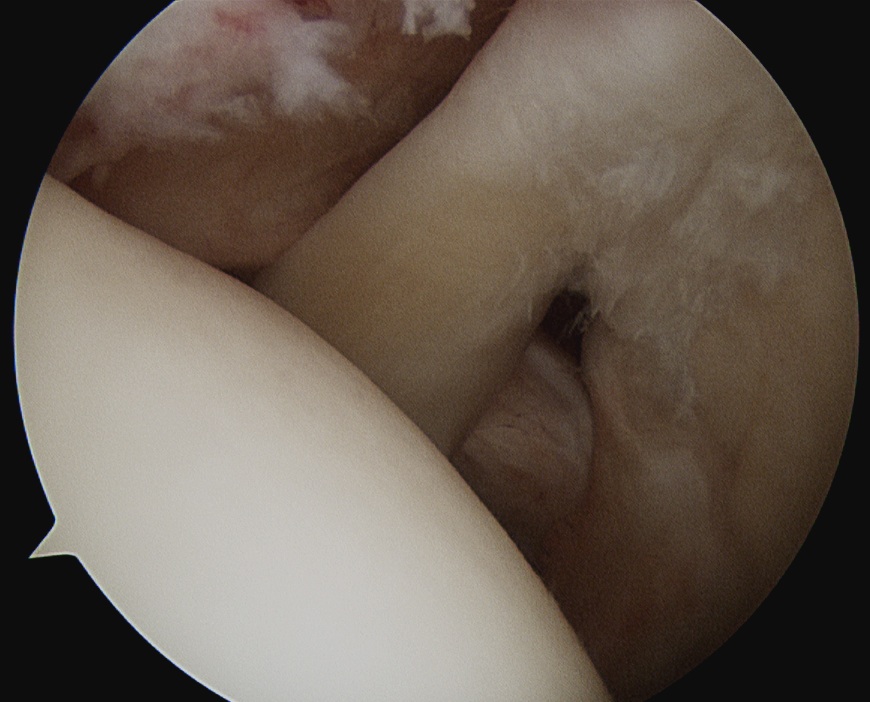

Tendonopathy